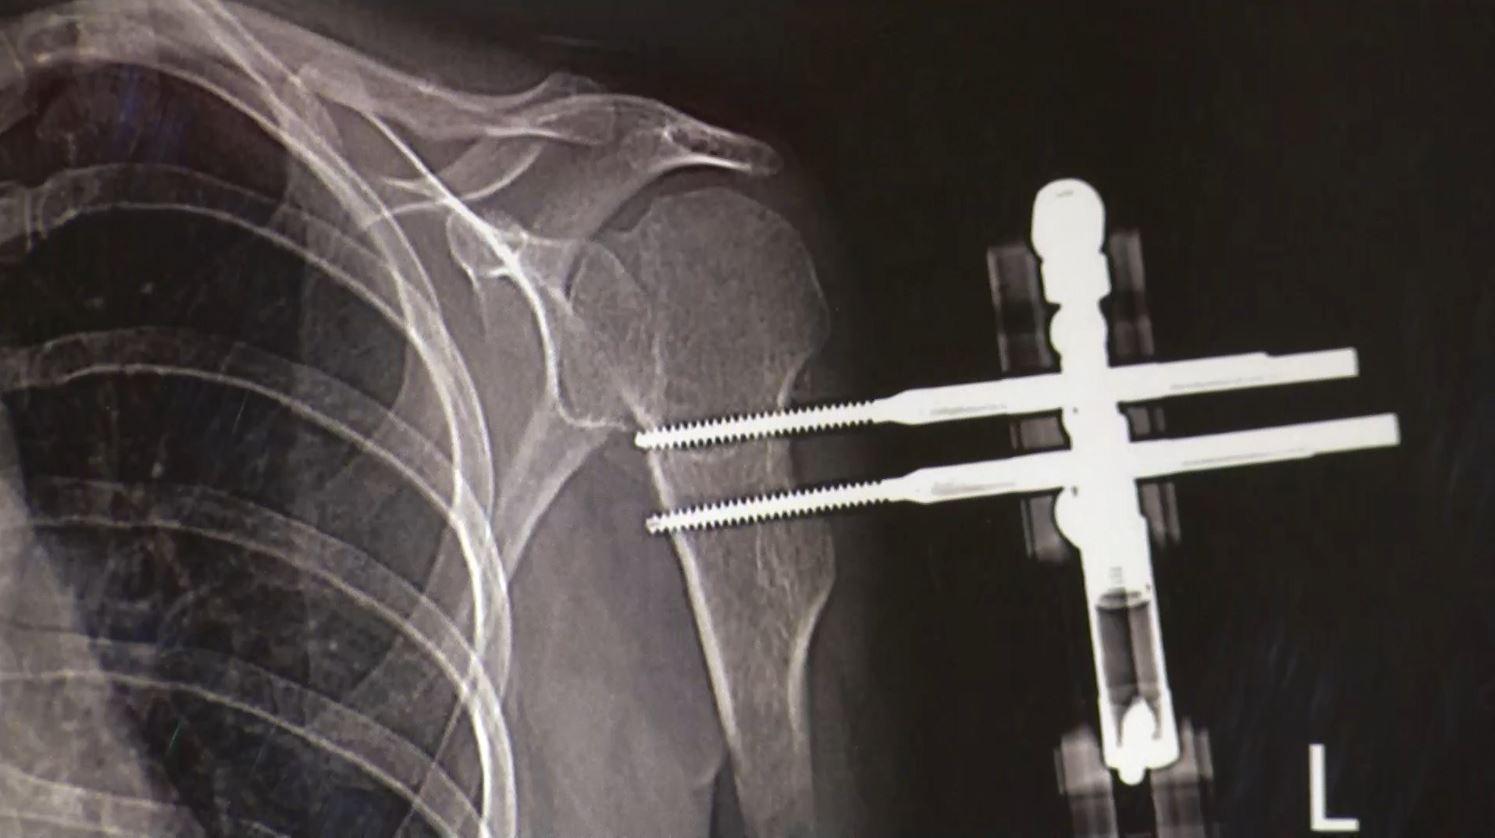

Kozmetik boy uzatma ameliyatı hakkında açıklamalarda bulunan Op. Dr. Halil Buldu, “Boy uzatma ameliyatında kemikte bir kese oluşturuluyor. Oluşturulan bu keseyi vücut kendisi doldurarak iyileştiriyor. Vücut kendi kemiğiyle boyunu uzatıyor. Tamamen fizyolojik bir kemik dokusu doluyor. Kozmetik boy uzatma ameliyatı herhangi bir kazadan sonra gerçekleşmiyor. Kişinin kendi isteği ile gerçekleşen bir ameliyat. Her operasyonda olduğu gibi boy uzatma operasyonlarında da risk payı her zaman vardır. Herhangi bir komplikasyon meydana gelmemesi için bütün önlemleri alıyoruz. Profesyonel bir ekibe sahibiz” dedi.

Çocukluk çağındaki belirli hastalıklara bağlı oluşan kısalıklara, 5 yaşında bile ameliyat yaptıklarını söyleyen Halil Buldu, “Dünyadaki rekorlardan birisi olduğunu düşündüğüm 62 yaşında Avrupa’da yaşayan bir hastamıza boy uzatma ameliyatı yaptık. Her yaş grubuna uzatma yapabiliyoruz. Boy uzatma oranları üst bacak ve alt bacağa göre değişir. Hastanın ilk boyu ve esnekliğine göre de uzatma oranı değişebilir. Yaklaşık 10 santimetre uzaması olan bir hasta 6 ay sonra normal hayatına dönmüş olur” ifadelerini kullandı.

13 santimetreye kadar uzatmayı vaat ettiklerini kaydeden Op. Dr. Halil Buldu sözlerine şöyle devam etti:

“Boy uzatma ameliyatına engel olabilecek hastalıklar var. İmmün sisteminde zayıflık oluşturabilecek bir kronik hastalığı ve ciddi bir metabolik hastalığı olan kişilerde boy uzatma ameliyatı gerçekleşmeyebilir. Enfeksiyon oluşacak durumlarda ameliyatı yapmak istemiyoruz.”